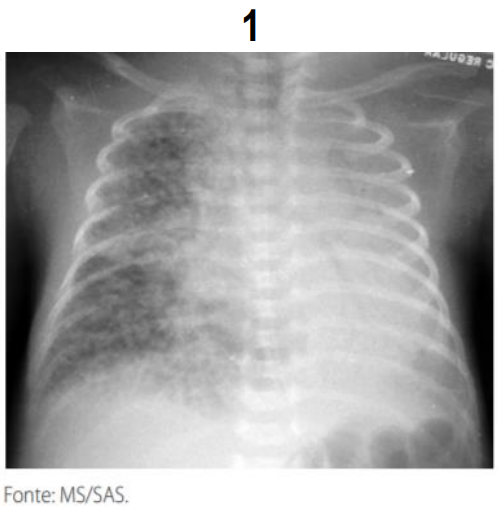

A radiografia de tórax é o exame de eleição para o diagnóstico das várias formas de SEAr. É fundamental, também, para a determinação do tamanho e da extensão da coleção de ar e da coexistência de outras entidades que possam facilitar ou perpetuar o escape de ar, além de permitir o acompanhamento evolutivo e avaliar a eficácia da terapêutica adotada. Na grande maioria dos casos o aspecto radiológico é típico, sendo possível definir o diagnóstico com relativa facilidade. Analise as imagens radiológicas com sinais patognomônico e assinale a alternativa da doença associada